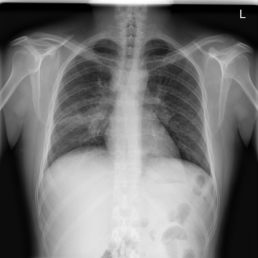

The wide variety of in-distribution and out-of-distribution data in medical imaging makes universal anomaly detection a challenging task. Recently a number of self-supervised methods have been developed that train end-to-end models on healthy data augmented with synthetic anomalies. However, it is difficult to compare these methods as it is not clear whether gains in performance are from the task itself or the training pipeline around it. It is also difficult to assess whether a task generalises well for universal anomaly detection, as they are often only tested on a limited range of anomalies. To assist with this we have developed nnOOD, a framework that adapts nnU-Net to allow for comparison of self-supervised anomaly localisation methods. By isolating the synthetic, self-supervised task from the rest of the training process we perform a more faithful comparison of the tasks, whilst also making the workflow for evaluating over a given dataset quick and easy. Using this we have implemented the current state-of-the-art tasks and evaluated them on a challenging X-ray dataset.